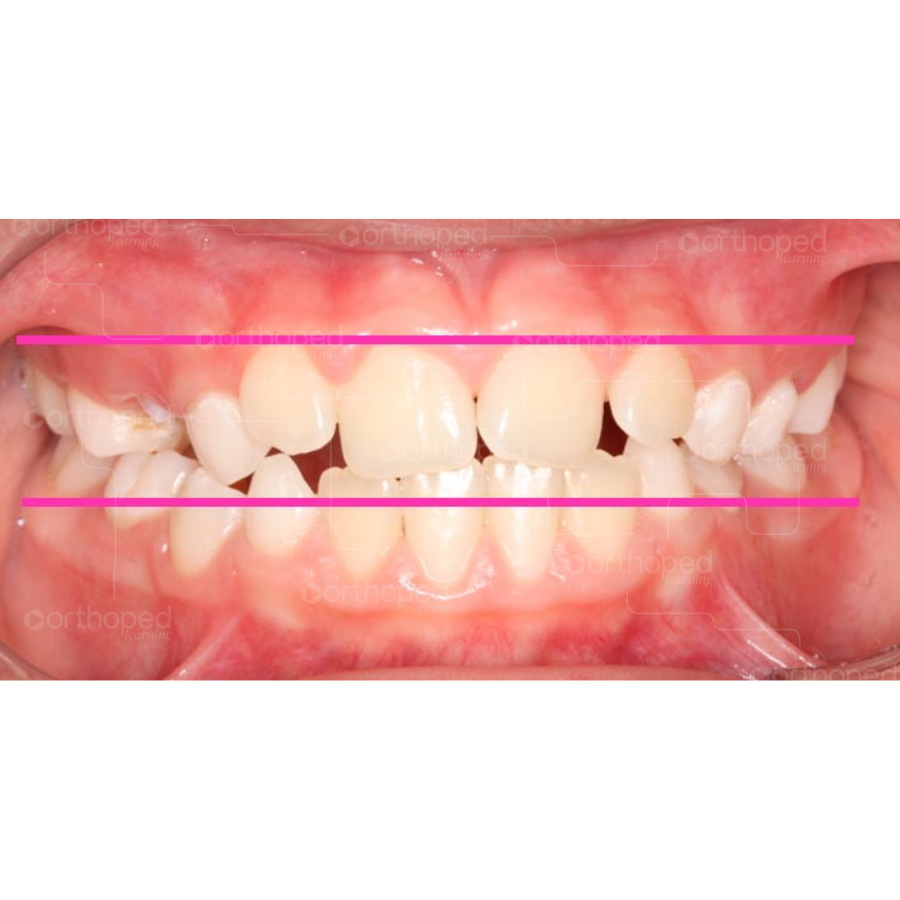

Observe na imagem que essa relação não é observada na região de dentes, mas ligeiramente acima (ou abaixo – no arco inferior) desses, na base alveolar.

Linhas rosas simulam a dimensão transversa (amplitude – largura) da maxila e da mandíbula, apresentando relação transversa satisfatória entre as bases ósseas.